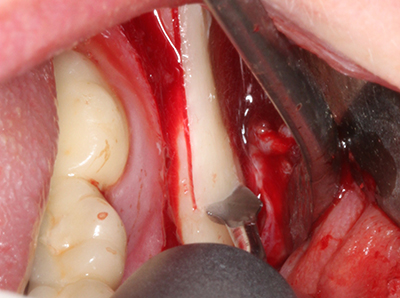

Fig. 1: preparazione di una copertura ossea con Piezomed (W&H Salisburgo, Austria).

Fig. 3: la separazione basale del blocco è più semplice con i raccordi appositamente angolati.